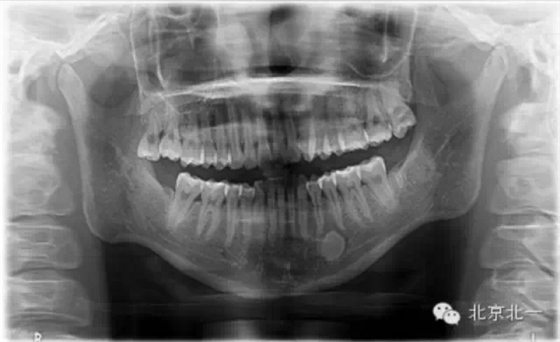

先看一例病例。頜骨內(nèi)單發(fā)高密度影像。是什么?能不能影響種植, 骨島是什么鬼?需要怎么處理?

【口腔種植】致密性骨炎/牙骨質(zhì)增生/骨島如何鑒別?

頜骨三種高密度影像的鑒別